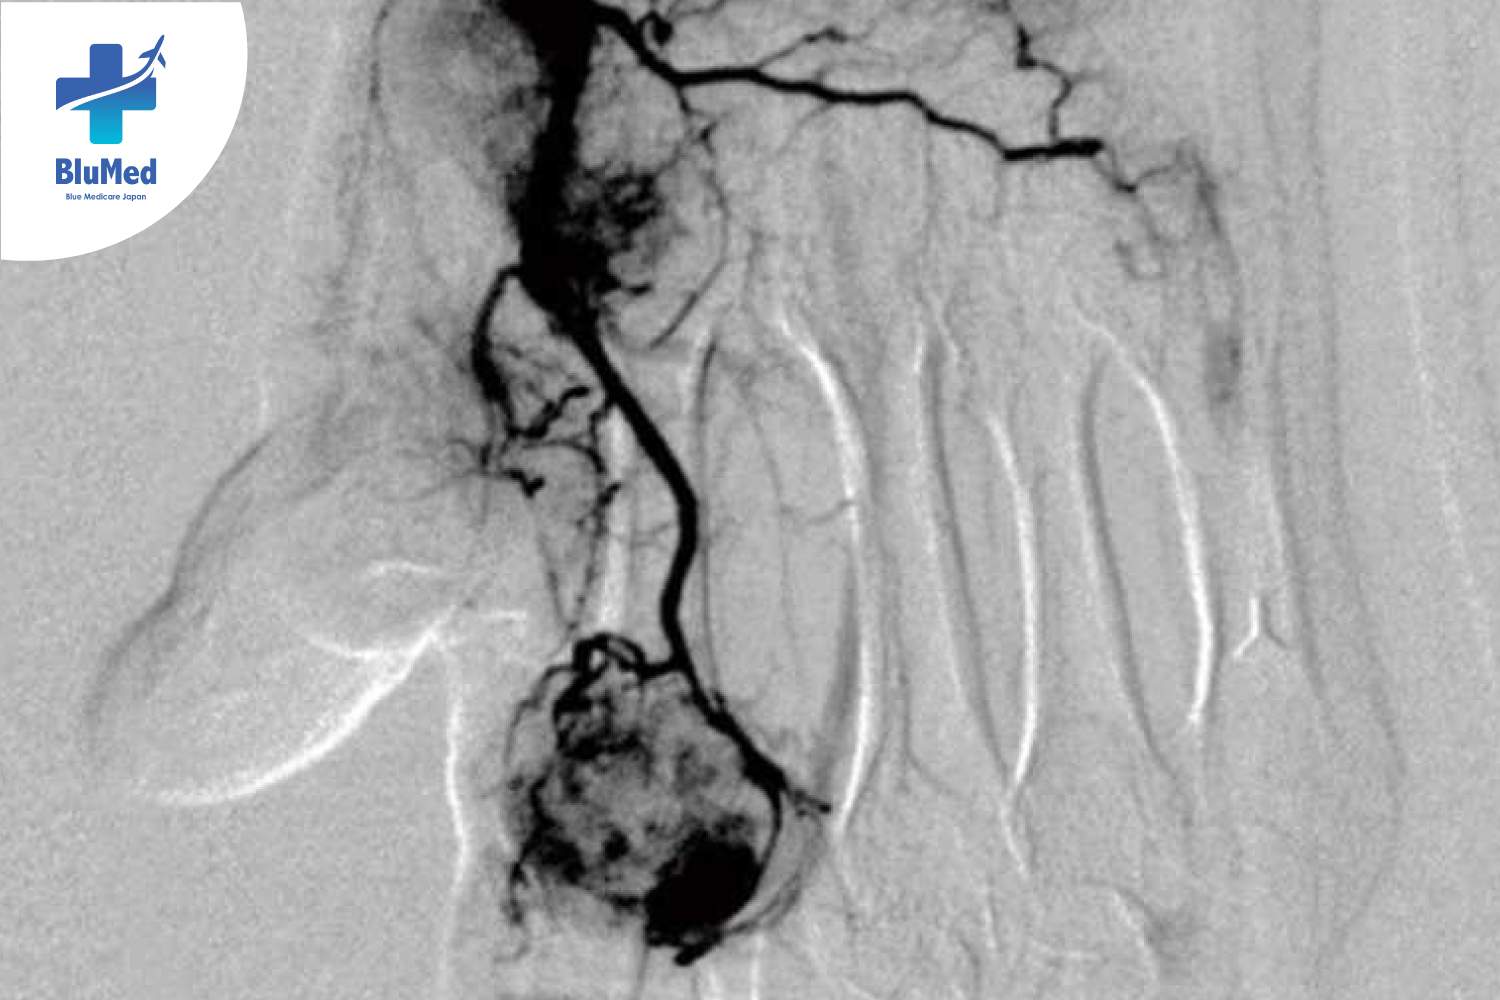

TAME Technique เป็นแนวทางการดูแลอาการปวดเรื้อรังจากญี่ปุ่น พัฒนาโดย Dr. Yuji Okuno เป็นอีกทางเลือกสำหรับผู้ที่ต้องการดูแลอาการปวดโดยไม่ต้องผ่าตัด และเน้นการฟื้นตัวที่รวดเร็วโดยไม่กระทบชีวิตประจำวัน